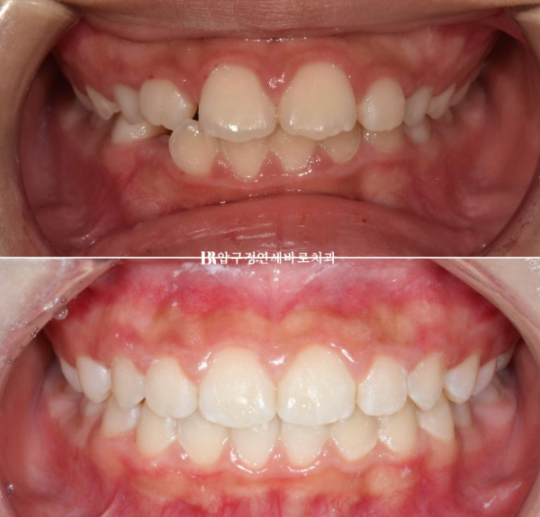

출처 아카이브 열기강남 소아교정 인비절라인 퍼스트 어린이 반대교합 교정 후기 들려드릴 압구정 교정치과입니다.

23.10~24.12

치료 중간 갑자기 예정에 없던 해외 이주 계획이 잡혔습니다.

치료를 1년 2개월 만에 마무리 해야 했지만 다행히 치료가 잘 끝났습니다.

23년 10월 만 11세 친구가 교정을 위해 첫 내원을 했습니다.

보호자가 보기에 가장 고치고 싶은 것은 돌출이고 앞니 사이즈가 큰 편 입니다.

24년 4월까지 6개월간 장치를 낀 후 모습입니다.

24.04

중심선은 잘 맞고

영구치들이 잘 내려오고 있습니다.

앞니 뻗친 부분도 개선이 되었습니다.

전 후 비교 보겠습니다.

치료 기간은 1년 2개월입니다.

뻗쳐있던 앞니 각도가 개선이 되면서 돌출이 해소가 되었습니다.